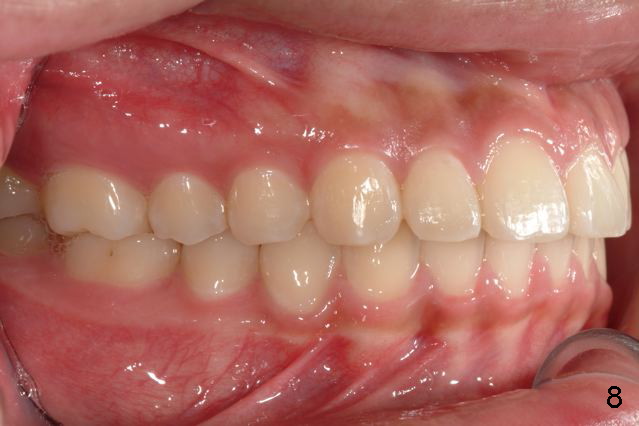

Answer: I was afraid tooth #8 would try to rotate (Fig.).  I do not like U bonded retainers as much as lower but I thought maybe in this case due to #8 initial position.  I have provided 2 removable retainers to fit over for insurance!

Excellent thinking.  According to the final photos, you must have done something to overcorrect the rotation of the two centrals.  Did you do it with purpose or by accident?  How did you do it, although Amy may not like it.  It seems to me that there is no practical way to overcorrect rotation.